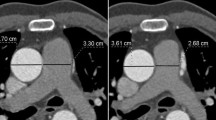

The largest transverse diameter perpendicular to the long axis of the main pulmonary artery (MPA) was measured at the level of pulmonary bifurcation. Distal to the bifurcation, the diameters of the right pulmonary artery (RPA) and the left pulmonary artery (LPA) were measured perpendicular to their long axis. The measurements were performed within proximal 2 cm distance from the lobar branching of the right and left pulmonary arteries (Fig. 1). The measurements of the aortic lumen were performed in the true axial plane perpendicular to the long axis of the vessel using oblique multiplanar reconstruction. The transverse diameters of ascending and descending aorta were measured at the level of pulmonary bifurcation (Figs. 2, 3). In order to facilitate evaluation of vascular structures in daily radiology practice, we tried to find out whether there was a constant value when the measurements of vascular diameters were compared with an internal reference. The thoracic (T) vertebra, which was at the level of pulmonary bifurcation, was used as the internal reference. The largest AP diameter of the T vertebra was measured (Fig. 4). The ratios obtained by division of each vessel diameter to the AP diameter of the T vertebra were calculated for each subject.